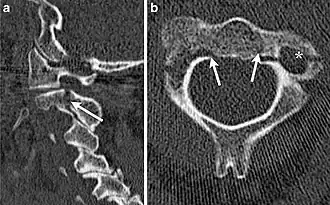

Tomografia computadorizada apresenta uma fratura do enforcado